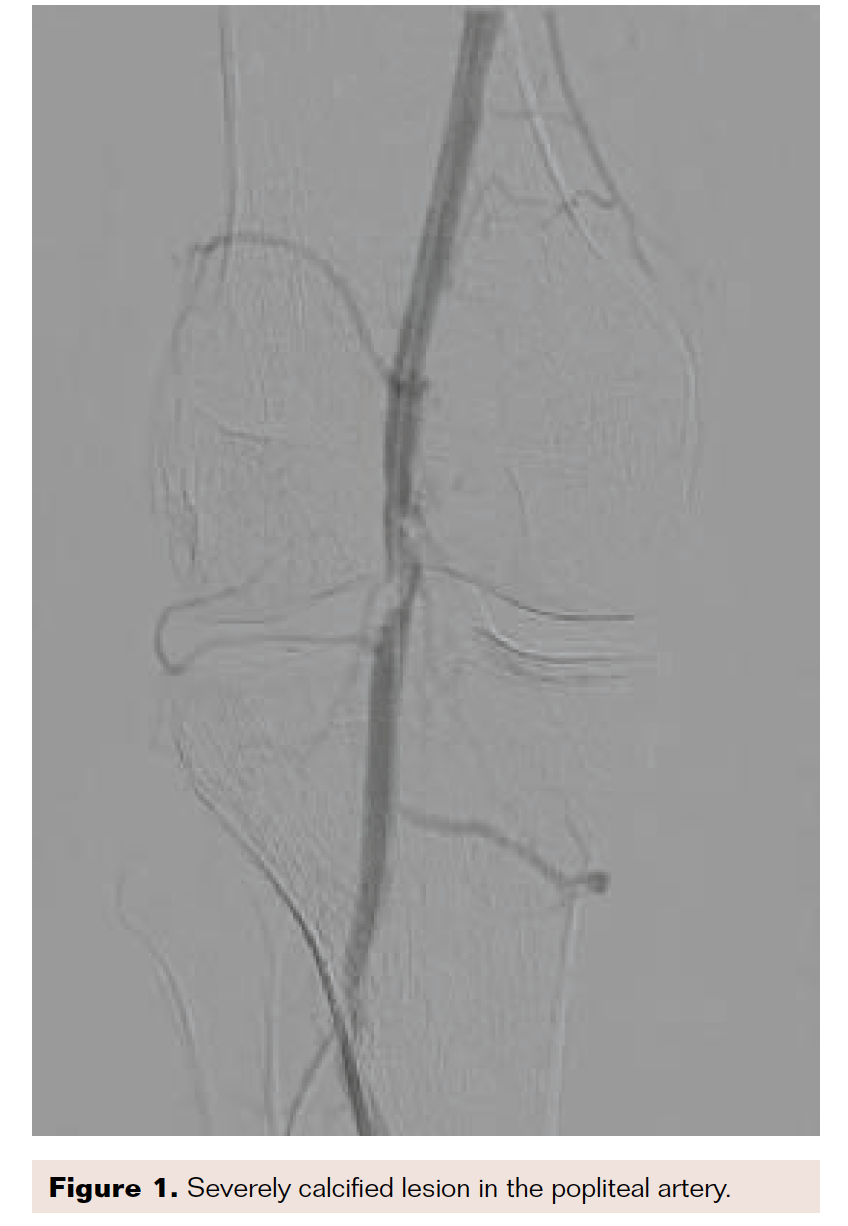

Intravascular lithotripsy is a new approach for controlling dissections, especially in severely calcified lesions. By creating ultrasonic waves, lithotripsy can effectively disrupt the sheets of calcium within plaque, and therefore improve the results of balloon angioplasty by minimizing both recoil and dissection, which are both more common in lesions with severe calcification.

I recently treated a patient with nonhealing ulceration of his right great toe. He had a severely calcified lesion in his popliteal artery, as demonstrated in Figure 1. Due to the calcification, I performed intravascular lithotripsy with a 5.5 mm × 60 mm balloon (Figure 2). After balloon inflation, the lesion had a residual type C dissection (Figure 3). Therefore, I placed 3 tack devices across the area of dissection (Figure 4). Final angiography demonstrated no residual dissection or recoil (Figure 5).